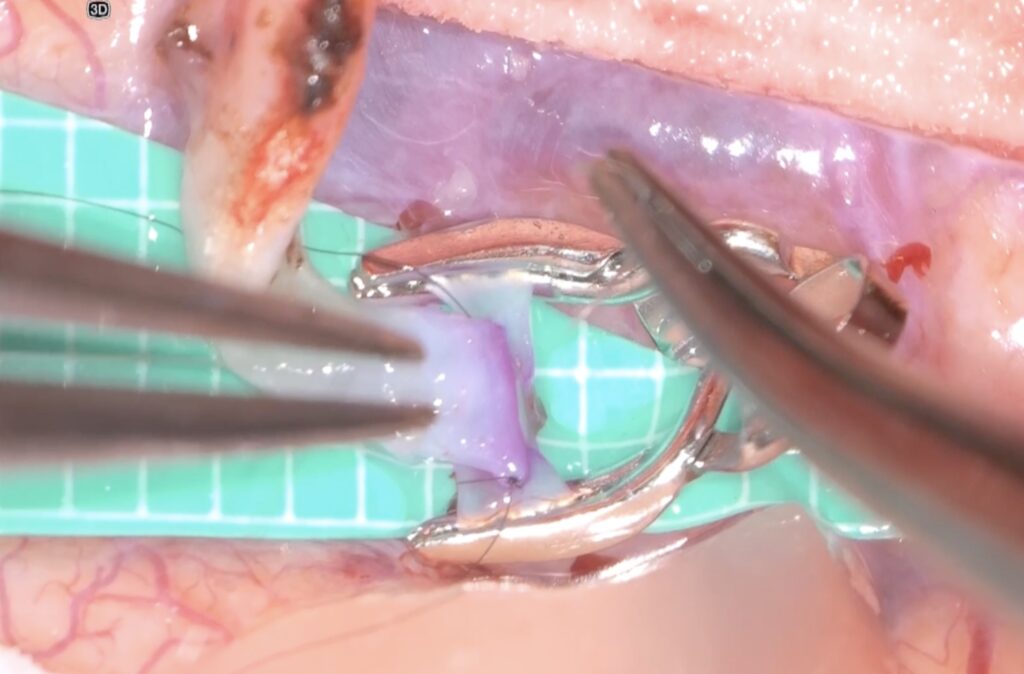

外視鏡を用いると吻合時にはデジタルズームをフットスイッチで入れると瞬時に高拡大にできます。

糸が通ったら、また瞬時にデジタルズームを切ります。

そして糸を結びます